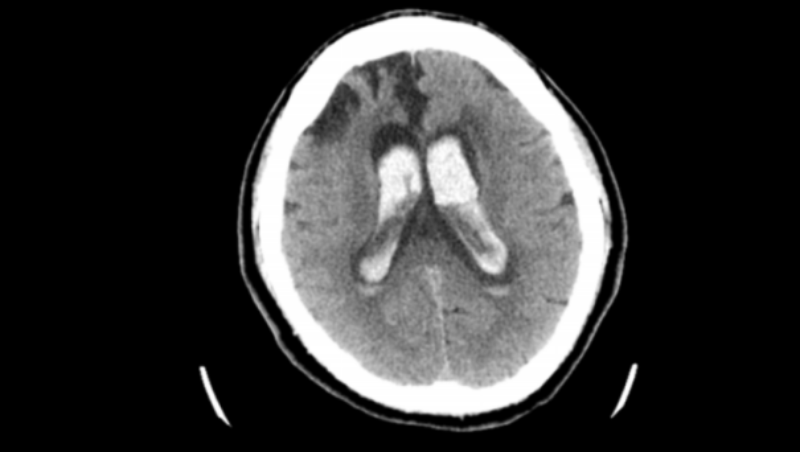

術(shù)后患者恢復意識了,能正?;卮饐栴},也能按照指令做動作就轉(zhuǎn)到普通病房去了。

拔除軟通道后-1

△軟通道后-2